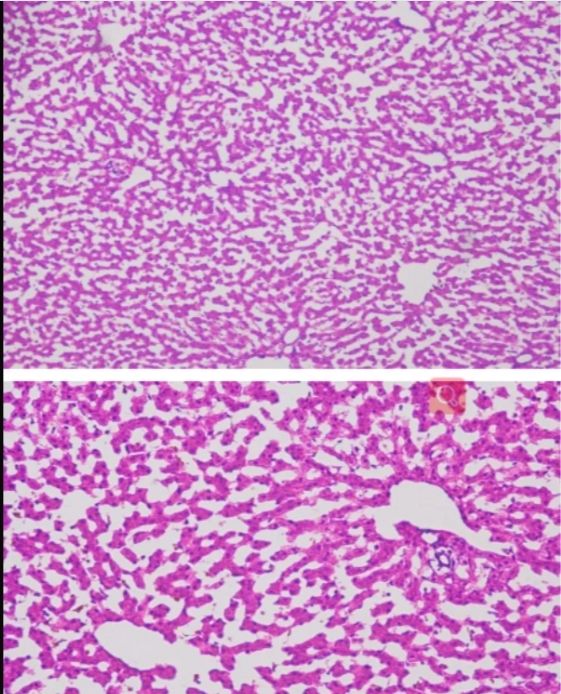

㈠觀察組織細胞的微觀結構:通過冰凍切片,研究人員可以獲得組織細胞的二維圖像,進而觀察和分析細胞的形態、大小、排列方式等微觀結構特征。這對于了解細胞的結構和功能,以及揭示疾病的發病機制和病理變化具有重要意義。